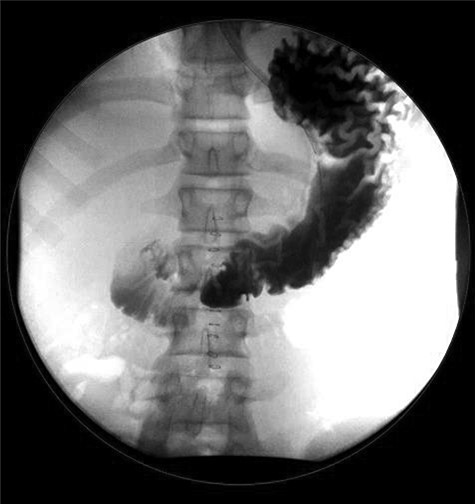

The patient was taken to the operating room for diagnostic laparoscopy. A 4-mm perforated duodenal ulcer by the pylorus with leaking bile was found and repaired with an omental patch. On postoperative Day (POD) 3, an upper gastrointestinal study was done, which showed no signs of obstruction or leak (Fig. 2). Serum gastrin levels were reported normal. On POD 4, he was started on a diet. He tested positive for Helicobacter pylori and was therefore treated with eradication triple therapy (proton pump inhibitor, amoxicillin and clarithromycin). The patient recovered uneventfully and was discharged home on POD 7, and was symptoms free at follow-up.

Upper gastrointestinal series (a)/small bowel follow-through (b): normal stomach demonstrated. Normal duodenum and proximal jejunal loops. No contrast extravasation identified. Oral contrast in the distribution of stomach, duodenum and proximal jejunal loops with no evidence for extravasation.